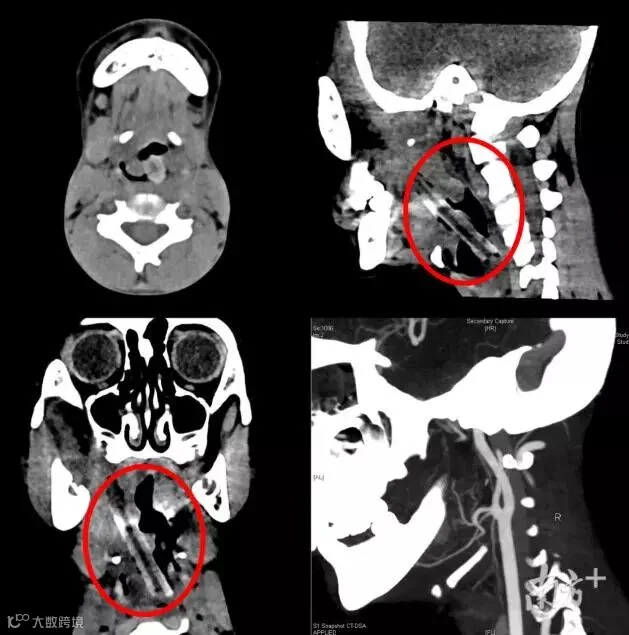

8岁男孩咽喉旁取出5厘米长树枝!竟是两年前摔倒时插入

“取出来了!树枝全部取出来了!”4月23日,在中山大学孙逸仙纪念医院手术室里,当一根长达5厘米的树枝从8岁小男孩小李的口中取出,手术室里医护人员一阵惊呼。

如果不是亲眼所见,大家都难以想象,这根大树枝,已经在小李的咽旁间隙“居住”超过两年,让他嘴巴难以张开正常进食,营养不良日渐消瘦……